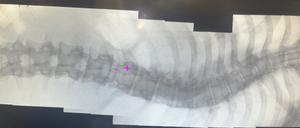

Etwa zwei Prozent der Bevölkerung leiden unter einer Verkrümmung der Wirbelsäule, der sogenannten Skoliose. So auch der 21-jährige Dane Storch. Wir waren live dabei, als er in Berlin operiert wurde.